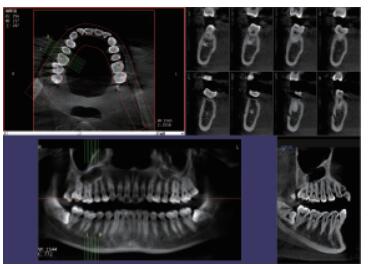

在口腔影像等細分領域,口腔CBCT的成像質量優于CT和普放。CBCT的X線利用率更高,且生成的圖像具備很高的各項同性空間分辨率。口腔CBCT能夠針對局部斷層曲面重建生成清晰無重疊的斷層影像以及3D影像,成像效果更好,有助于醫生的診斷,對于種植、綜合診斷、正畸等牙科診斷均有較大幫助。口腔CBCT技術優勢如下:

三維重建任意斷層

專有三維重建算法,可提供任意位置高清斷層影像。

高清口腔全景影像

通過三維容積影像,提取高清口腔全景影像。

多平面組合重建

可同時觀察軸向面、冠狀面和矢狀面圖像,方便臨床診斷。